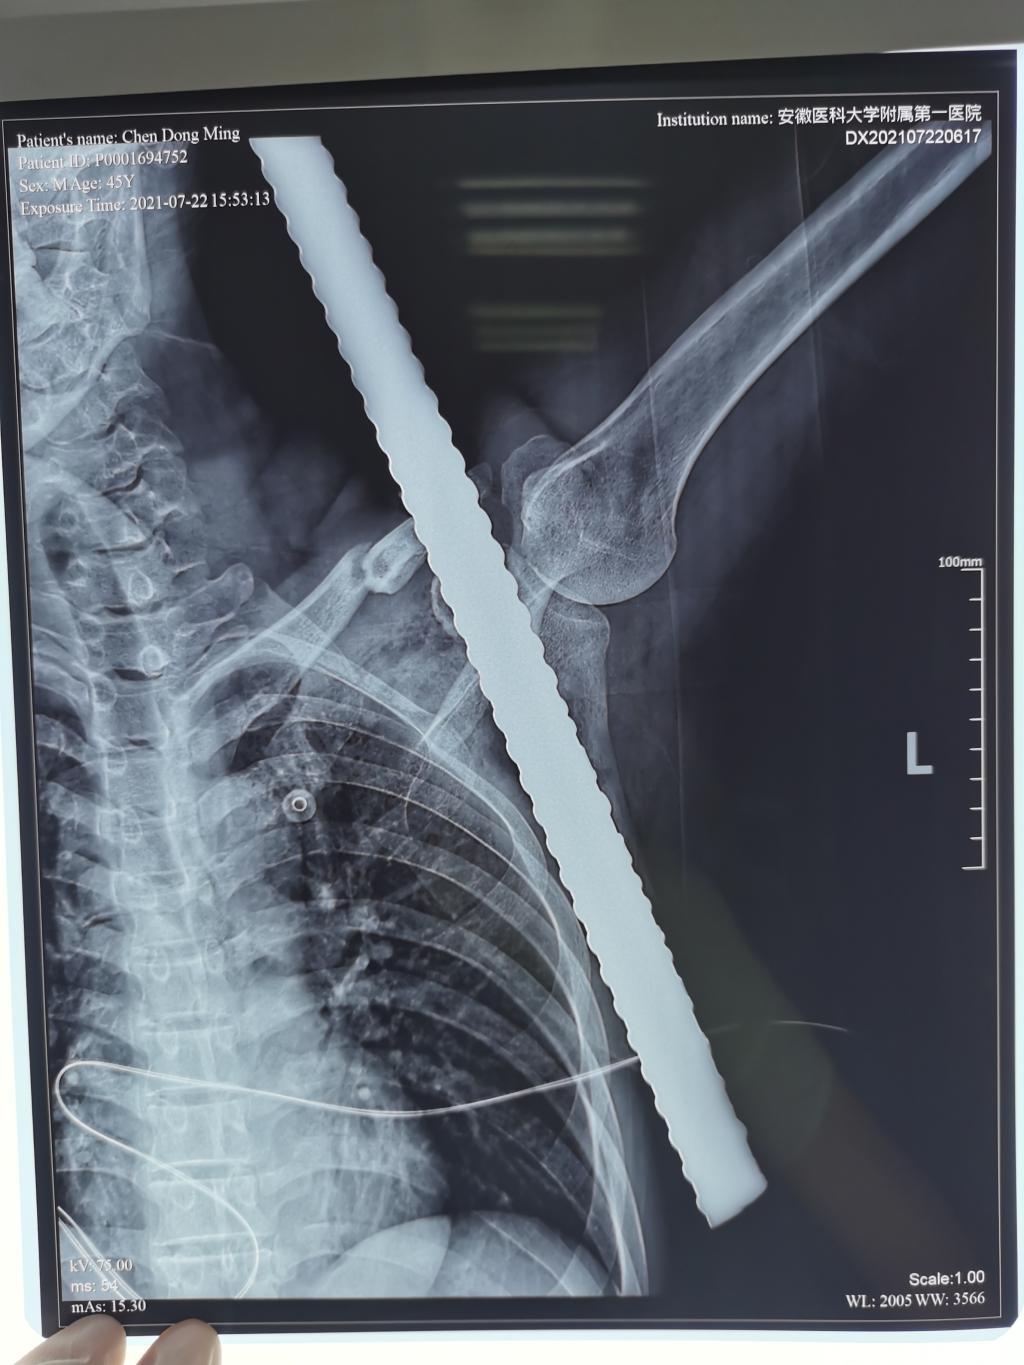

7月22日下午4时许,医院急诊室送入了一名特殊的患者,一根50厘米长,2.5厘米粗的钢筋,赫然贯穿在患者陈先生的左肩。拇指粗的钢筋从陈先生左肩后方插入,左侧前方胸壁穿出。

我院急诊科迅速启动绿色通道,经初步影像学检查后,胸外科、创伤骨科等多学科迅速响应会诊,创伤骨科住院总医师严超及二线班张月雷副主任医师经仔细查体和阅片,发现患者的锁骨骨折,钢筋从胸壁前方胸大肌深处贯穿,幸运地避开了锁骨下方及腋窝的重要血管神经。经急诊科完善术前检查后,由创伤骨科、手术室、麻醉科多团队协作,手术历经一小时,钢筋成功被取出。术后患者左上肢活动自如,末梢感觉及运动正常。因钢筋污染较重,患者伤口后续仍有感染风险,将继续在创伤骨科住院观察。